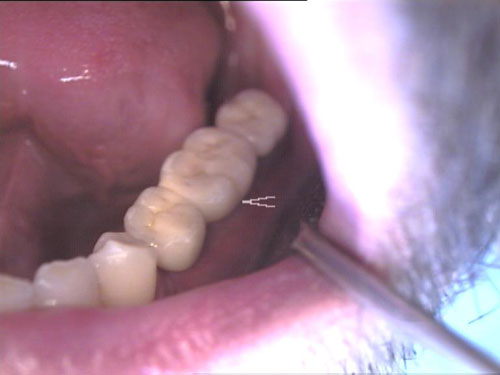

Zahnimplantate 2